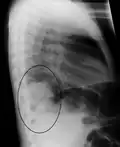

- Right lower lobe pneumonia as seen on a lateral CXR